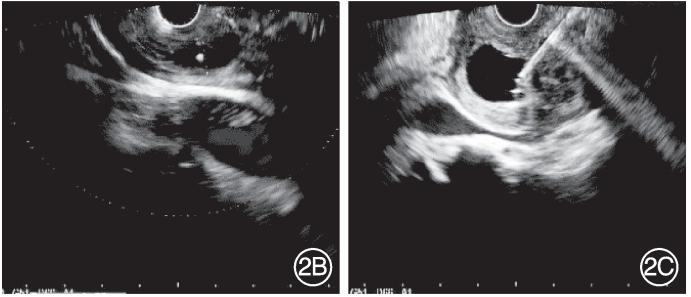

入院后完善相关实验室检查,脂肪酶284.2 U/L(参考值:13~60 U/L)、淀粉酶125.4 U/L(参考值:0~150 U/L),肿瘤标志物以及免疫球蛋白G亚型等均未见明显异常。复查超声内镜提示胰腺与十二指肠间可见一囊性病变,囊肿截面大小3.02 cm×1.46 cm,囊肿与胰管相通;胰腺钩突部胰管扩张,内可见高回声病变,伴声影;胰腺实质可见点状偏高回声;胆总管未见扩张;于囊性病变处行EUS‑FNA,抽取褐色液体2.8 mL后可见囊肿缩小(图2);随后行ERCP,在胰管内置入1枚支架。术后禁食水,给予抗炎、抑酸、抑制胰酶分泌、补液等治疗。术后6 d复查,脂肪酶122.3 U/L,淀粉酶70.2 U/L,患者腹痛及背部疼痛症状较刚入院时有明显缓解。6个月后超声内镜复查,胰管无明显扩张,其内未见高回声影(图3),行胰管支架拔除术。

图3 术后6个月后复查超声内镜未见胰管明显扩张,胰管内未见高回声影